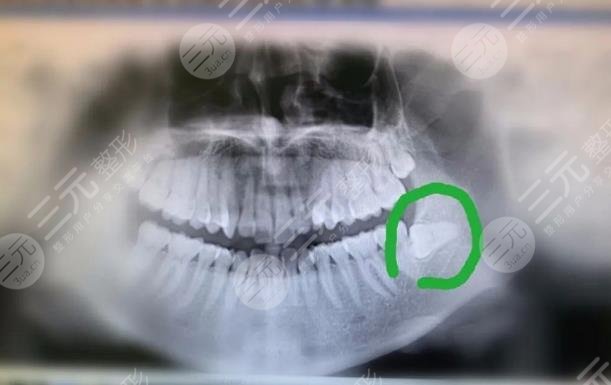

后来我朋友说上海太平洋口腔医院专业性强,实力强劲,于是我便来这家医院。医生给我拍了x光照片,从X光照片当中可以明X的看出我的智齿长歪了,如果任凭发展下去只会造成疼痛感。医生建议拔除智齿,一开始我还很担心把智齿会牵扯到神经,会对神经造成伤害,疼痛感会十分强烈,但事实证明我是多想了,在拔智齿的过程当中,医生护士较为的温柔,整个操作极为娴熟。